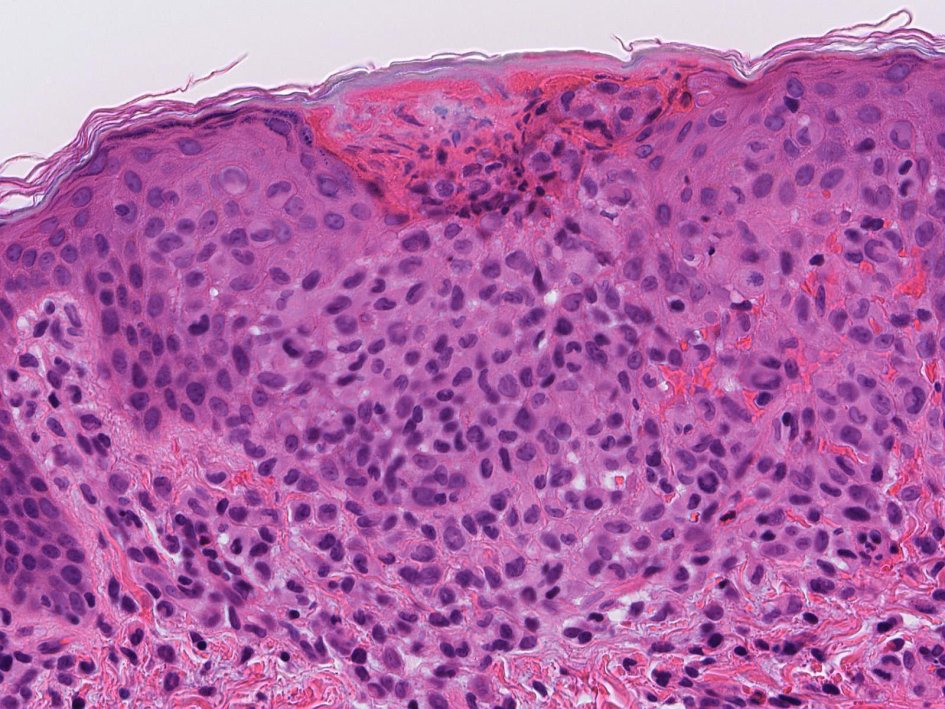

0歳女児 皮膚に1mm大の丘疹が多発, びらんを伴っている.肝脾腫あり

皮膚組織所見

病理組織診断:Langerhans cell histiocytosis, multifocal multisysem disease

増殖細胞は単核性で核は切れ込み,ひだ,捻じれを示す他, 分葉状, グローブ状のこともある。細胞質は好酸性。細胞異型をみることもあるが通常は異型がない。核分裂像は病変によりさまざま。